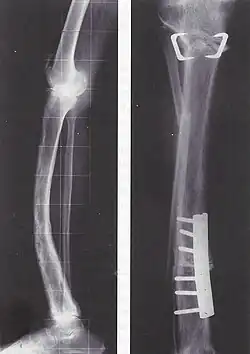

Paget-Tibia bei 73-jähriger Patientin; Korrekturosteotomien

Die Behandlung ist symptomatisch mit schmerzlindernden und entzündungshemmenden Medikamenten wie Nichtsteroidalen Antirheumatika, Entlastung des Knochens, Krankengymnastik und gegebenenfalls operativer Stabilisierung von Knochenbrüchen. Tritt keine Besserung der Symptome ein, können Medikamente den Verlust der Knochenmasse verhindern und Schmerzen lindern; Bisphosphonate und Calcitonin hemmen den Knochenabbau und können bei rechtzeitiger, regelmäßiger Einnahme Deformierungen verhindern. Neuerdings stehen auch Bisphosphonate (Zoledronat, Aclasta®; Pamidronat, Aredia®) zur intravenösen Infusion zur Verfügung. Sie ersetzen die tägliche Tabletteneinnahme. Die einmalige Infusion von Zoledronat hat eine Wirkungsdauer von über einem Jahr. Ergänzend werden Vitamin D und Calcium verschrieben. Bei einer besonders schweren Schädigung der Hüfte kann ein Hüftgelenkersatz erforderlich sein.